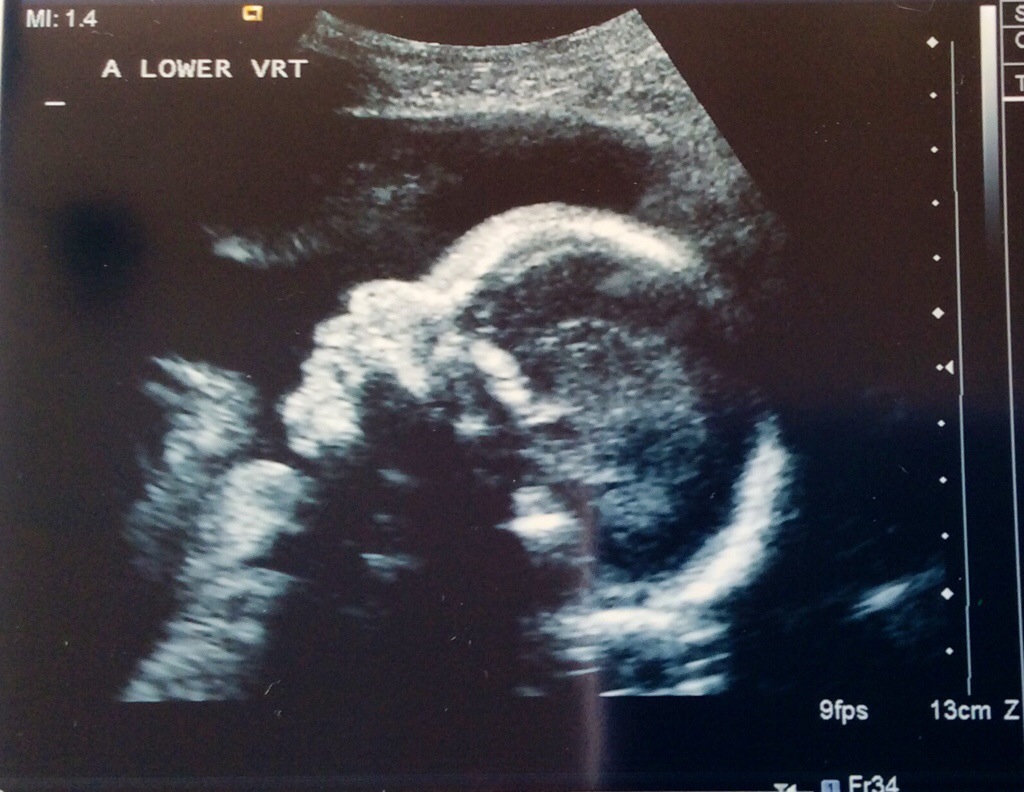

Monday we had our fetal echo and it looks like both babies hearts are just fine. Sigh of relief! Baby A still has her small calcification, but the radiologist was not concerned at all and said not to worry. We also had another growth check at this same ultrasound appointment. Baby A is estimated to be 1 lb 14 oz and Baby B is estimated to be 2 lbs. Baby A is in the 67th percentile and Baby B is in the 83rd percentile. They are growing and we couldn’t be happier!

Baby A in profile